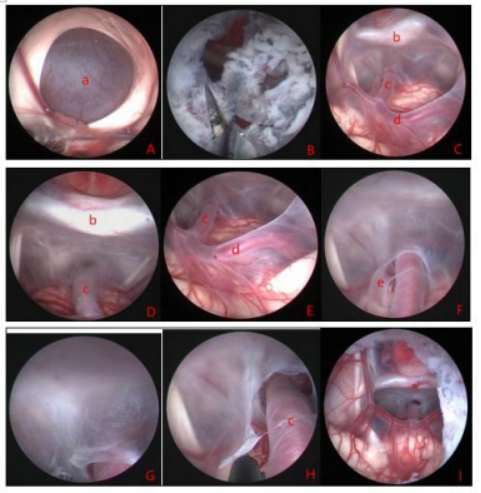

图8.显示鞍上囊肿伴脑积水术中所见。A:鞍上囊肿顶部; B:囊肿顶部瘘口;C、D、E:通过顶部造瘘口进入囊肿内部,可见囊肿内部的解剖结构;F:囊肿底部基底动脉旁的裂隙活瓣;G、H:囊肿底壁造瘘;I:底部造瘘完毕,从侧脑室观察上方和下方的造瘘口。A:囊肿壁 b:鞍背 c:基底动脉 d:大脑后动脉 e:裂隙活瓣